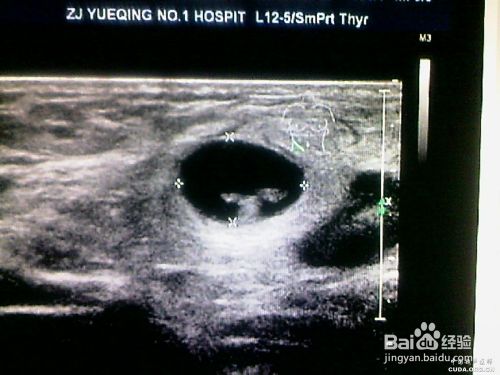

大多数是发现无痛性乳腺质硬包块就诊,且不活动性包块,边界不清;包块一般通过自己检查发现的,自己检查手法:用手掌面(非手指尖),对乳房外上、外下、内下、内上,最后中央乳头区域全面检查。注意:不用手指捏抓乳房组织(很多患者就是抓到包块就诊,检查其实就是乳房腺体,因为腺体本来就是一个一个排列的,这样很不准确)。

乳头溢液,非妊娠期乳头流液体,如果是红色的就特别注意了,可能就是癌;注意:不管你乳头流出什么颜色的液体,一定要到医院就诊,检查,以免耽误病情。